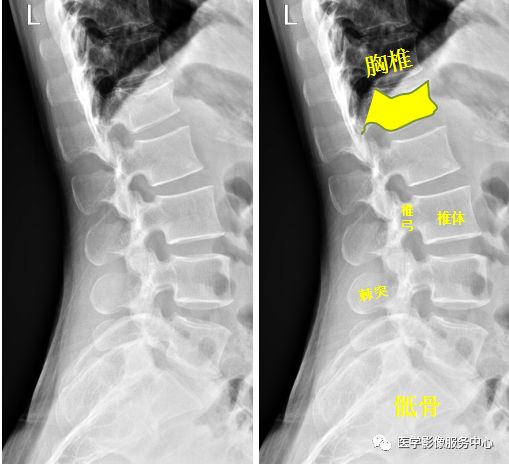

脊柱

图片

腰椎侧位示:第1腰椎呈前低后高楔形改变。腰椎第1椎体陈旧性压缩性骨折。

Warmreminder: 陈旧性骨折多在左其他检查时发现,压缩性骨折因受伤时重力向下所致,腰椎、胸椎易发生。

(小妙招此患者腰痛来院,询问病史,十年前从楼上坠落,休息一段时间后无大碍,并没有行检查。)